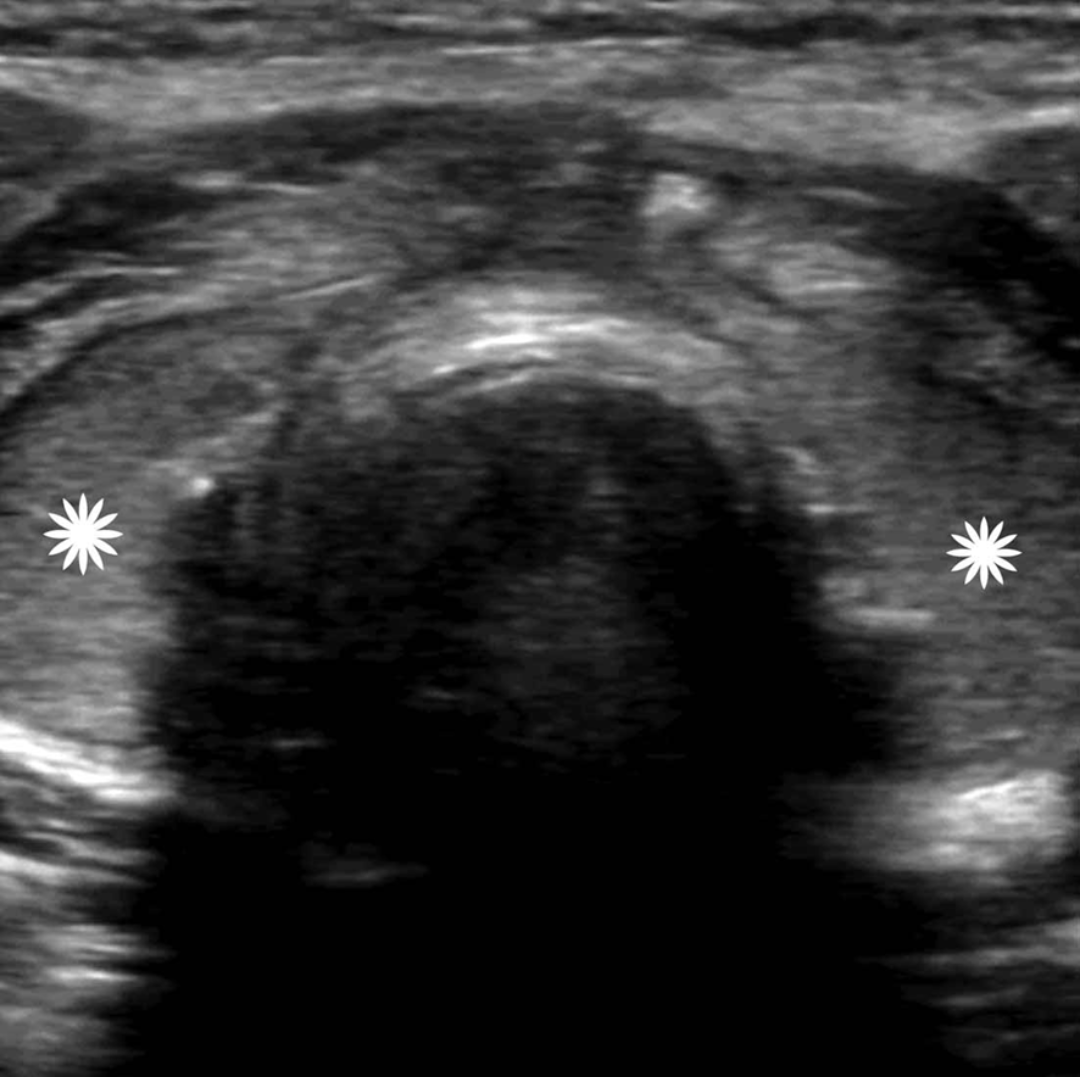

Figura 6. Ecografía transversal de una paciente de 36 años tras tiroidectomía y disección del compartimento central por CAP con punción con aguja fina no concluyente, pero con imagen positiva. La Ecografía, obtenida 25 días después de la cirugía, muestra imágenes ecogénicas uniformes en ambos lechos de tiroidectomía (asteriscos) sugerentes de presencia de agentes hemostáticos.